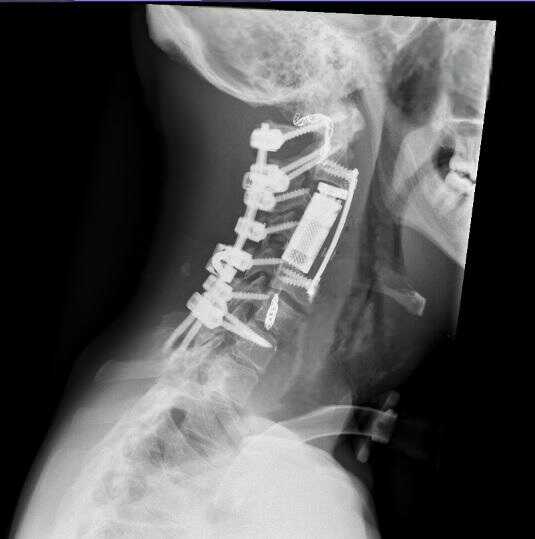

وفي المرحلة الجراحية، تم إجراء تثبيت خلفي للعمود الفقري من الفقرة العنقية الأولى وحتى السابعة، مع تحرير النخاع الشوكي وتأمين استقرار الفقرات، وبعد ذلك، أُجري استئصال كامل للورم والفقرات المصابة بطريقة "الاستئصال الكامل في كتلة واحدة" عبر المدخل الأمامي للعنق، تلاه تعويض الفقرات باستخدام قفص فقري تمددي، مع تثبيت أمامي لضمان الثبات الكامل للعمود الفقري.

وأكد البربراوي أن هذه العملية تُعد الأولى من نوعها في الأردن والمنطقة، ولا تُجرى إلا في المراكز المتقدمة على مستوى العالم، نظرًا لتشريح الورم المعقد، إذ شملت استئصال أكثر من فقرة عنقية إضافة إلى الشريان الفقري المصاب المجاور للورم.